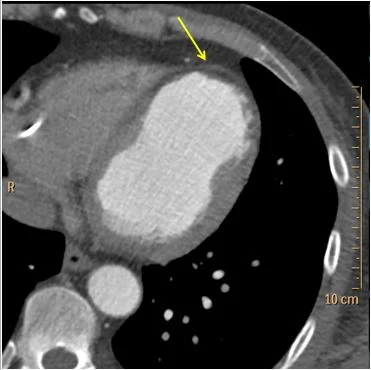

60 year old male presented to the ED with shortness of breath. CT scan of the chest obtained with contrast to evaluate for aortic dissection. He has a known old LAD territory STEMI from 3 years prior, at which time he received LAD stent placement. The old MI is obvious on CT, and I am told, equally obvious on the EKG.

Conventional CT shows wall thinning and apparent hypoenhancement in the distal anterior wall and apex. On spectral images, using the virtual non-contrast image, we can tell there is deposition of fat in the subendocardium (negative HU values). Fat deposition is a common finding in old MI. There is also markedly decreased iodine uptake in the old MI, relative to the normal myocardium.

Conventional CT: Clear old distal anterior and apical infarct (yellow arrow). Wall is thin and hypoenhancing relative to normal myocardium.